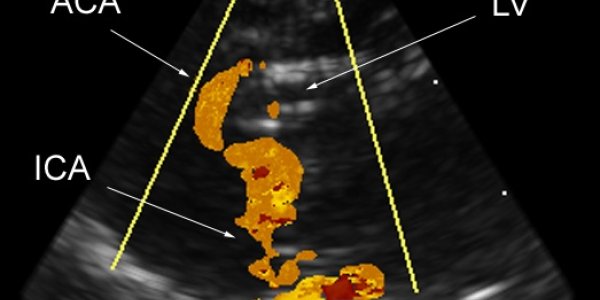

The Brain Scope - Seeing The Brain In 3-D

Biomedical engineers at Duke's Pratt School of Engineering have adapted a three-dimensional ultrasound scanner that might guide minimally invasive brain surgeries and provide better detection of a…